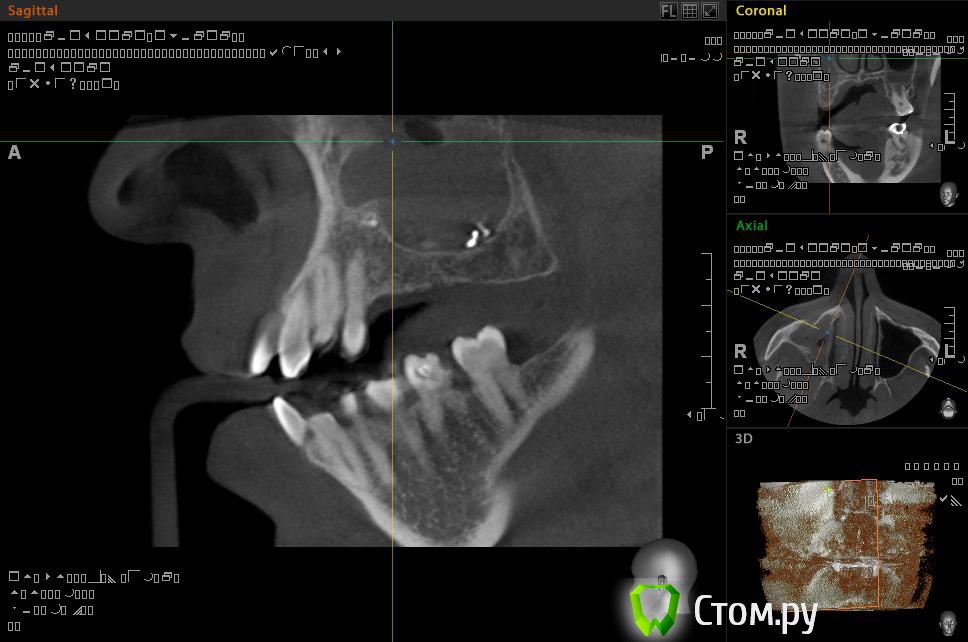

Евений Опубликовано 22 ноября, 2013 Поделиться Опубликовано 22 ноября, 2013 (изменено) Здравствуйте!В 2011 году делал КТ. Заполнена тотально правая пазуха, у медиальной стенки инородное тело овоидной формы, в центре которого объект металлической плотности, мелкие объекты на нижней стенке пазухи. Полипы у носового хода.После этого была радикальная гайморотомия на правой пазухе. Обнаружили застарелый хронический процесс, творожистые массы, поставили холеастому. Гистология операционного материала показала наличие грибка.По своей инициативе сделал 3d-томографию на picasso trio.Рентгенолог сказал про уровень в пазухе и инородное тело.КТ делал во время простуды, был насморк.Сходил на консультацию к профессору, который меня оперировал. Внимательно осмотрев носовую полость он ничего не нашел. Про КТ сказал, что это могут быть корни зубов. Пломбировочный материал отрицает, как и перед операцией. На данный момент - простуда, и оперированную пазуху закладывало больше чем здоровую. Выделения прозрачные, потом желтые и оранжевые.. Из минусов, как и раньше стекает слизь по задней стенке. Вопрос такого плана: Что за загогулины в правой оперированной пазухе? Целесообразно ли делать микрогайморотомию после радикальной, или если будут делать то опять радикальную?Спрашиваю потому, что уже не знаю к кому обращаться у нас в Архангельске. Вроде, операция радикальная была под контролем эндоскопа, уж должны были всё проверить и достать. Делал операцию академик, светило медицины в области хирургической стоматологии и онкологии.И еще - а стоит ли вообще делать вторую операцию? Возможно вред от вмешательства и наркоза перетянет пользу операции. Спасибо!ССЫЛКА НА РЕЗУЛЬТАТЫ ПИКАССО ТРИО http://dfiles.ru/files/qc62dn476 Изменено 22 ноября, 2013 пользователем Евений Ссылка на комментарий

АнтонТЛТ Опубликовано 22 ноября, 2013 Поделиться Опубликовано 22 ноября, 2013 Найдите хорошего ЛОРа, который нормально уберет остатки пломбировочного материала 2 Ссылка на комментарий